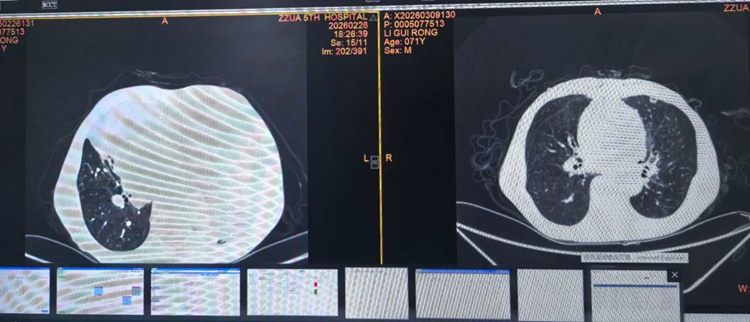

640 (4)_副本

▲ 术前(左侧)与术后(右侧)肺窗对比

640 (5)_副本

▲ 术前(左侧)与术后(右侧)纵隔窗对比